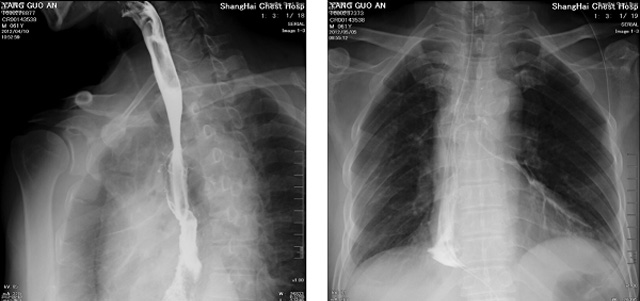

DR設(shè)備在2020年的新冠疫情中,加速了市場調(diào)整。以醫(yī)院為主的向二三級市場轉(zhuǎn)變。特別是小巧靈活的移動DR設(shè)計,填補CT和磁共振不能三維檢查的缺點,滿足內(nèi)科外科特別是骨科的影像診斷需求。還有懸吊DR設(shè)備CT斷層射線系統(tǒng)。使用錐束成像技術(shù)對整個脊柱和整個下肢進行了體積三維掃描。無需使用對比劑,即可使用X射線呼吸功能標測來模擬模擬氣流和血流,以評估患者的肺動脈血栓。